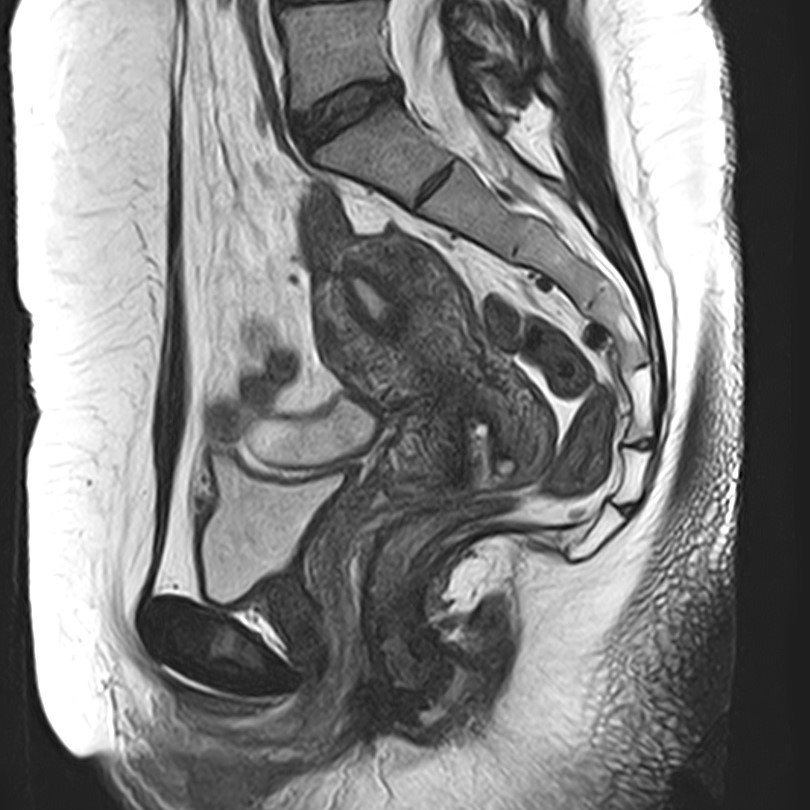

Магнитно-резонансная томография копчика является высокоинформативным методом выявления причин возникновения кокцигодинии. В клинике «Доступная медицина» диагностика осуществляется на новейшем высокопольном томографе закрытого типа TOSHIBA VANTAGE TITAN 1,5 Тесла, обеспечивающем высочайшее качество изображений исследуемой зоны.

Томограф позволяет детально визуализировать как костные структуры копчика, так и окружающие мягкие ткани данной анатомической области, включая мышцы, связки, нервные сплетение, сосуды и прилежащие органы малого таза. МРТ копчика дает возможность диагностировать патологические процессы в самом копчике и выявить их взаимосвязь с патологией окружающих структур.